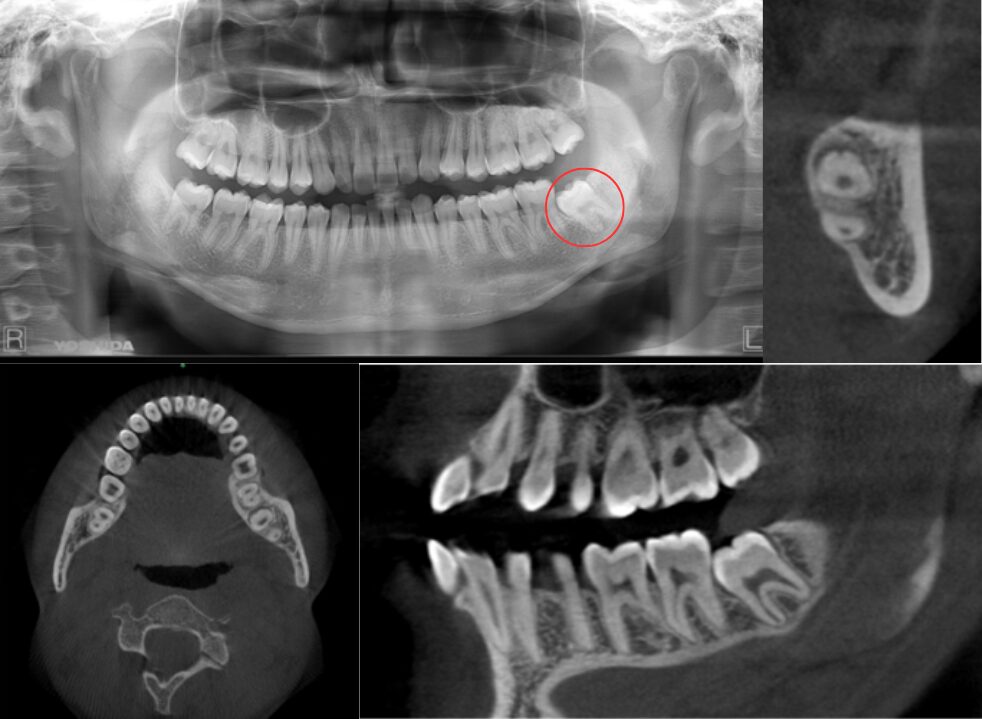

一部歯茎に埋伏している症例

| 患者情報 | 22歳 男性 |

| 手術時間 | 5分 |

| 治療内容 | 親知らず抜歯 |

| グレゴリー分類 | Ⅱ position A |